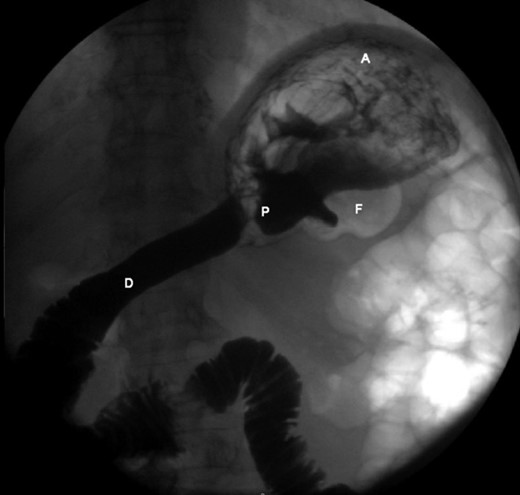

The patient’s leucocyte count and serum amylase presented mildly elevated. Chest radiograph revealed an elevated left hemi-diaphragm. Abdominal radiographs demonstrated a spherical stomach, presupposing an upward position of the pylorus (Fig. 1).

Abdominal radiograph, demonstrating a spherical stomach, presupposing an upward position of the pylorus.